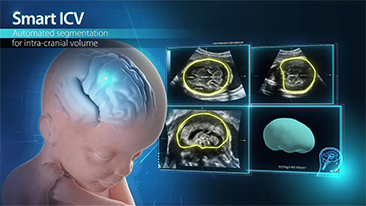

Com a plataforma ZST+ avan?ada, as solu??es inteligentes full-stack do Nuewa s?o projetadas especialmente para melhorar a saû¤de da mulher durante toda a gesta??o, desde o perûÙodo que antecede ao que procede û gravidez e û recupera??o pû°s-parto, a fim de oferecer diagnû°sticos abrangentes e eficientes para atender aos desafios clûÙnicos cada vez mais exigentes.